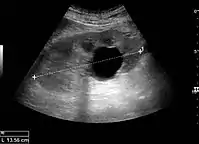

Masses are seen as a distortion of the normal renal architecture. Most renal masses are simple cortical renal cysts with a round appearance and a smooth thin capsule encompassing anechoic fluid. The incidence increases with age, as at least 50% of people above the age of 50 have a simple cyst in one of the kidneys. Cysts cause posterior enhancement as a consequence of reduced attenuation of the ultrasound within the cyst fluid (Figure 5). The simple cyst is a benign lesion, which does not require further evaluation.[1]

Figure 5. Simple renal cyst with posterior enhancement in an adult kidney. Measurement of kidney length on the US image is illustrated by '+' and a dashed line.[1] Figure 5. Simple renal cyst with posterior enhancement in an adult kidney. Measurement of kidney length on the US image is illustrated by '+' and a dashed line.[1]